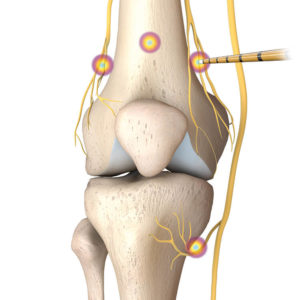

Gekühlte Radiofrequenz-Therapie

- Ultraschall-gesteuert am Knie

Ziel ist es, chronische Schmerzsignale gezielt auszuschaltenNach exaktem Platzieren der Sonde werden sensorische, schmerzleitende Nerven thermisch über die ausgesendete Radiofrequenz gezielt stillgelegt.

Da die Sonden wassergekühlt sind, entstehen im Gewebe Temperaturen lediglich zwischen 45 und 80 Grad – das ist sehr gewebeschonend, Nekrosen treten nicht auf.Der kugelförmige Wärmebereich an der Sondenspitze weist im Vergleich zu anderen thermischen Koagulationsverfahren ein 5malig größeres Volumen auf, so ist die Wahrscheinlichkeit, einen schmerzleitenden Nerv auch bei anatomisch abweichendem Verlauf zu erwischen, außerordentlich viel größer – genau das bildet sich in der hohen Erfolgsquote der Methode ab.